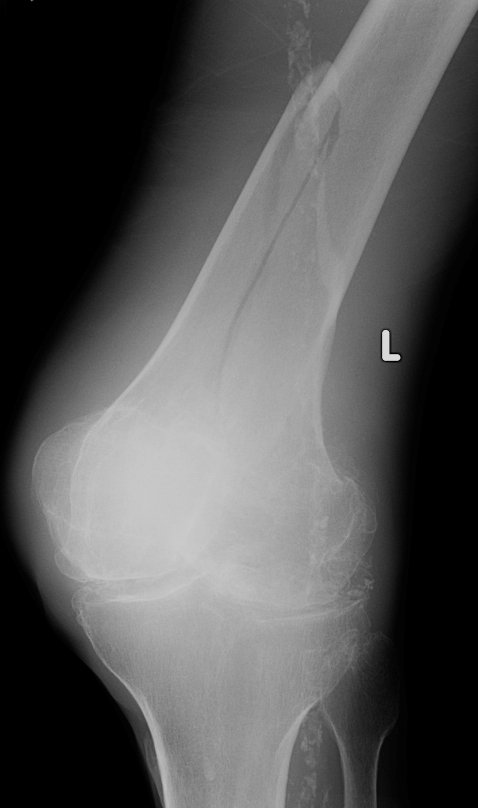

Return to Femoral Shaft Fracture